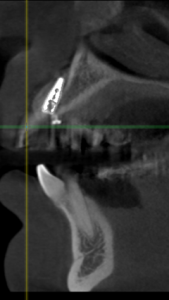

This video demonstrates implant placement in the esthetic zone combined with simultaneous guided bone regeneration (GBR). The case focuses on surgical decision-making, specifically how to determine when a staged approach is indicated versus when simultaneous implant placement and GBR can be predictably performed.

The procedure is presented step by step, including flap design and management, defect assessment, membrane selection and stabilization, flap advancement, and suturing techniques. Emphasis is placed on achieving tension-free closure and maintaining hard and soft tissue contours critical for esthetic success.